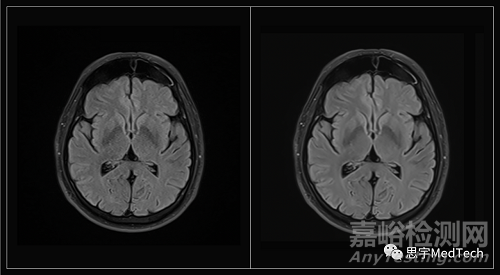

該公司使用了多步驗(yàn)證過程,其中五名放射科醫(yī)生對(duì)AI的性能進(jìn)行了定性和定量分析。

紐約大學(xué)放射科創(chuàng)新主任兼先進(jìn)成像創(chuàng)新與研究中心主任Daniel Sodickson博士表示:“Ezra Flash獲得FDA批準(zhǔn)是一個(gè)重要的里程碑——這標(biāo)志著醫(yī)學(xué)成像使用方式的重大變化。隨著時(shí)間推移,成像速度逐漸增加已經(jīng)為患者和醫(yī)生帶來(lái)了無(wú)數(shù)好處。然而,到目前為止,成像主要用于在其他癥狀已經(jīng)出現(xiàn)后診斷和表征疾病。”

“相反,Ezra正在將MRI作為一種早期檢測(cè)癌癥的工具,在出現(xiàn)癥狀之前進(jìn)行篩查——這種主動(dòng)監(jiān)測(cè)的安全網(wǎng)以前只對(duì)具有某些明確風(fēng)險(xiǎn)因素的患者開放。Ezra Flash將增加早期預(yù)警MRI的可及性,并且Ezra隨著時(shí)間推移重復(fù)掃描所產(chǎn)生的數(shù)據(jù)集將有助于防止假陽(yáng)性,并確保它提供的警告是適當(dāng)和可行的。”

▲(圖左為未使用AI技術(shù)形成的MRI圖像,圖右為Ezra Flash AI增強(qiáng)后圖像)